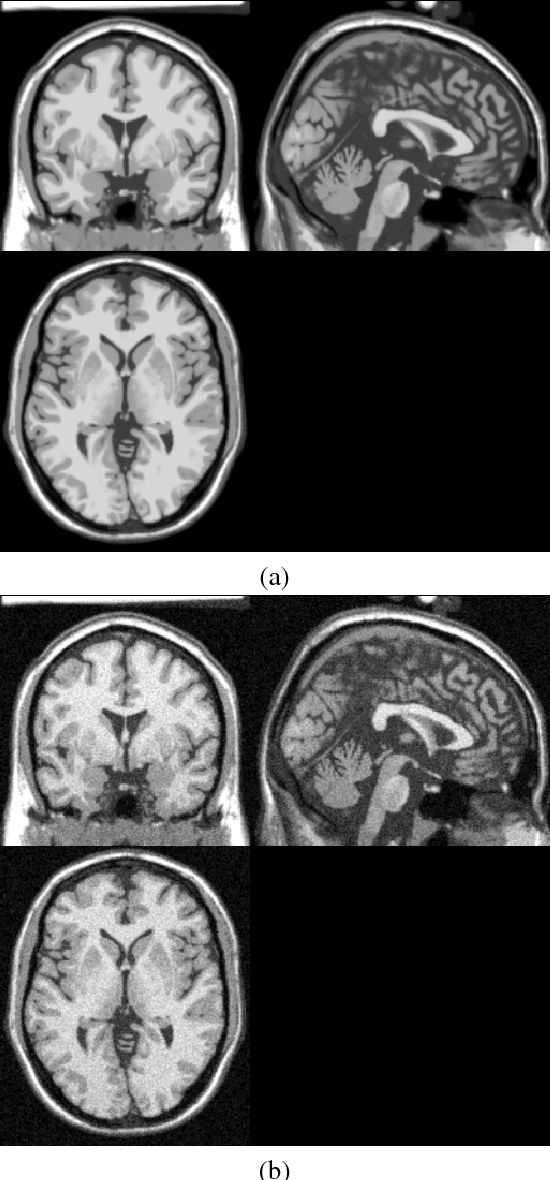

Abstract:High-frequency noise is present in several modalities of medical images. It originates from the acquisition process and may be related to the scanner configurations, the scanned body, or to other external factors. This way, prospective filters are an important tool to improve the image quality. In this paper, we propose a non-local weighted operational anisotropic diffusion filter and evaluate its effect on magnetic resonance images and on kV/CBCT radiotherapy images. We also provide a detailed analysis of non-local parameter settings. Results show that the new filter enhances previous local implementations and has potential application in radiotherapy treatments.